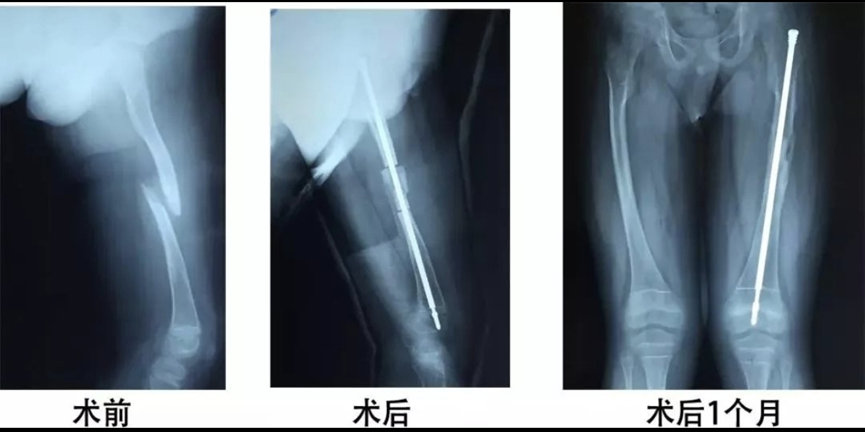

可延长髓内钉治疗成骨不全

目前可延长髓内钉常应用于患有成骨不全、骨纤维结构不良等骨脆弱、骨畸形等疾病儿童中。由于成骨不全、骨纤维不良等疾病常造成长骨段骨皮质菲薄脆弱,外支架及钢板的螺钉无法获得有力的把持,而可延长髓内钉采用螺纹设计,使髓内钉固定在长骨两端,避免了这一缺点。当对长骨畸形截骨矫形时,相对于其他矫形方式,可延长髓内钉采用从长骨两端进针,减少了手术范围及截骨次数,降低了软组织及骨膜的剥离带来的损伤,一定程度上促进了截骨或骨折部位的愈合。相比常规的髓内钉,可延长髓内钉由于其自身可延长性,在适应儿童骨骼生长发育上有着无可比拟的优势。可延长髓内钉可随着长骨生长而延长,提供了与儿童骨骼生长相适应的生物力学环境,降低了再骨折和畸形复发的发生率。有利于患者早期下床活动进行负重锻炼。